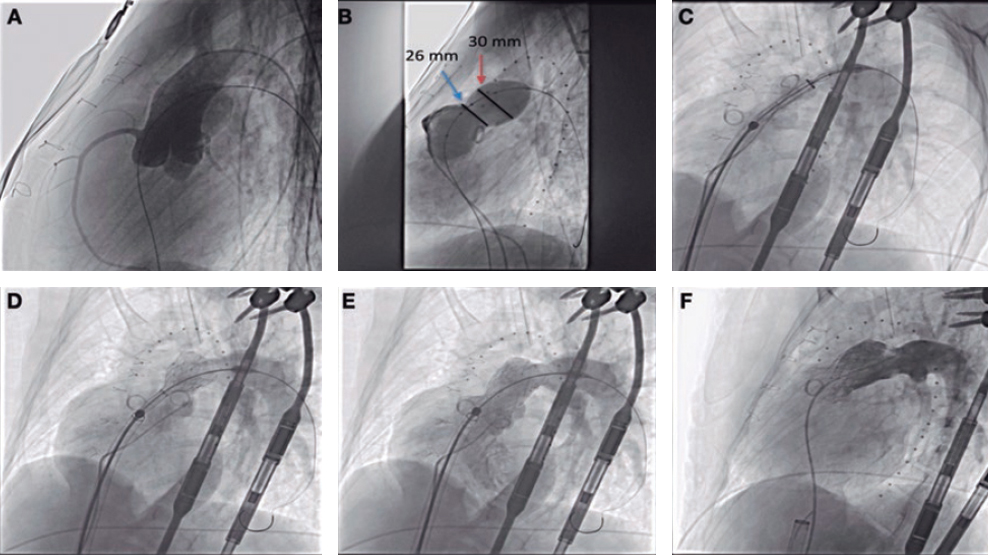

Left main coronary artery lesions

Five patients with left main coronary artery lesions were treated with the ICL balloon. Four were unprotected lesions and were treated under hemodynamic support using the Impella device (all of them showed a severely depressed ejection fraction and/or a right coronary artery chronic total occlusion). Device and clinical success were achieved in all cases.

Regarding the procedure, it should be noted that the crossing rate for the ICL balloon was 100% despite a high percentage of plaque preparation was required (62% balloon pre-dilatation, 27% rotational atherectomy). Recently, the combination of rotational atherectomy and ICL has been described as RotaTripsy, suggestive that these 2 calcium debulking techniques may be complementary, since rotational atherectomy facilitates the ICL balloon crossing, and the latter facilitates proper expansion in the presence of circumferential deep calcium plaques.9 The device success rate was 84% (100% in the Disrupt CAD II linical trial) and the clinical success rate was 95% (94% in the Disrupt CAD II trial). And most important of all, no major procedural complications were seen, which is consistent with the Disrupt CAD II trial results. The rupture of the ICL balloon during inflation occurred in 3 cases (12%) without associated complications, yet the rupture of the balloon has been described in a case report resulting in a type C coronary dissection; the interventional cardiologist needs to be aware of this lithotripsy-related potential complication.10 Intravascular imaging were performed in few cases probably because the operator thought it would be difficult to cross an especially severe and calcified lesion with the OCT or IVUS catheter. Consistent with the results of the Disrupt CAD I and II clinical trials and OCT substudy,5,11 it was confirmed that the modification of calcium and the presence of fractures lead to an acute area gain and favorable stent expansion in the lesions assessed through OCT in our series. Figure 1 shows the coronary angiography and OCT of one complex patient treated with ICL; the red arrows seen on figure 1D,E indicate calcium fractures after the ICL.

Figure 1. Intracoronary lithotripsy, angiography, and optical coherence tomography. Patient with severe coronary artery heart disease with severely depressed left ventricular ejection fraction previously treated with coronary artery bypass graft (venous graft-left anterior descending coronary artery, currently occluded). Treatment of left main coronary artery, left anterior descending artery, and diagonal branches. A: pre-intracoronary lithotripsy angiography. B: Impella-assisted PCI of left anterior descending coronary artery. Arrow indicates inflated lithotripsy balloon. C: successful final angiographic result after stenting. D, E and F: optical coherence tomography cross-sectional images of a post-lithotripsy calcified lesion. Red arrows indicate calcium microfractures after intracoronary lithotripsy.